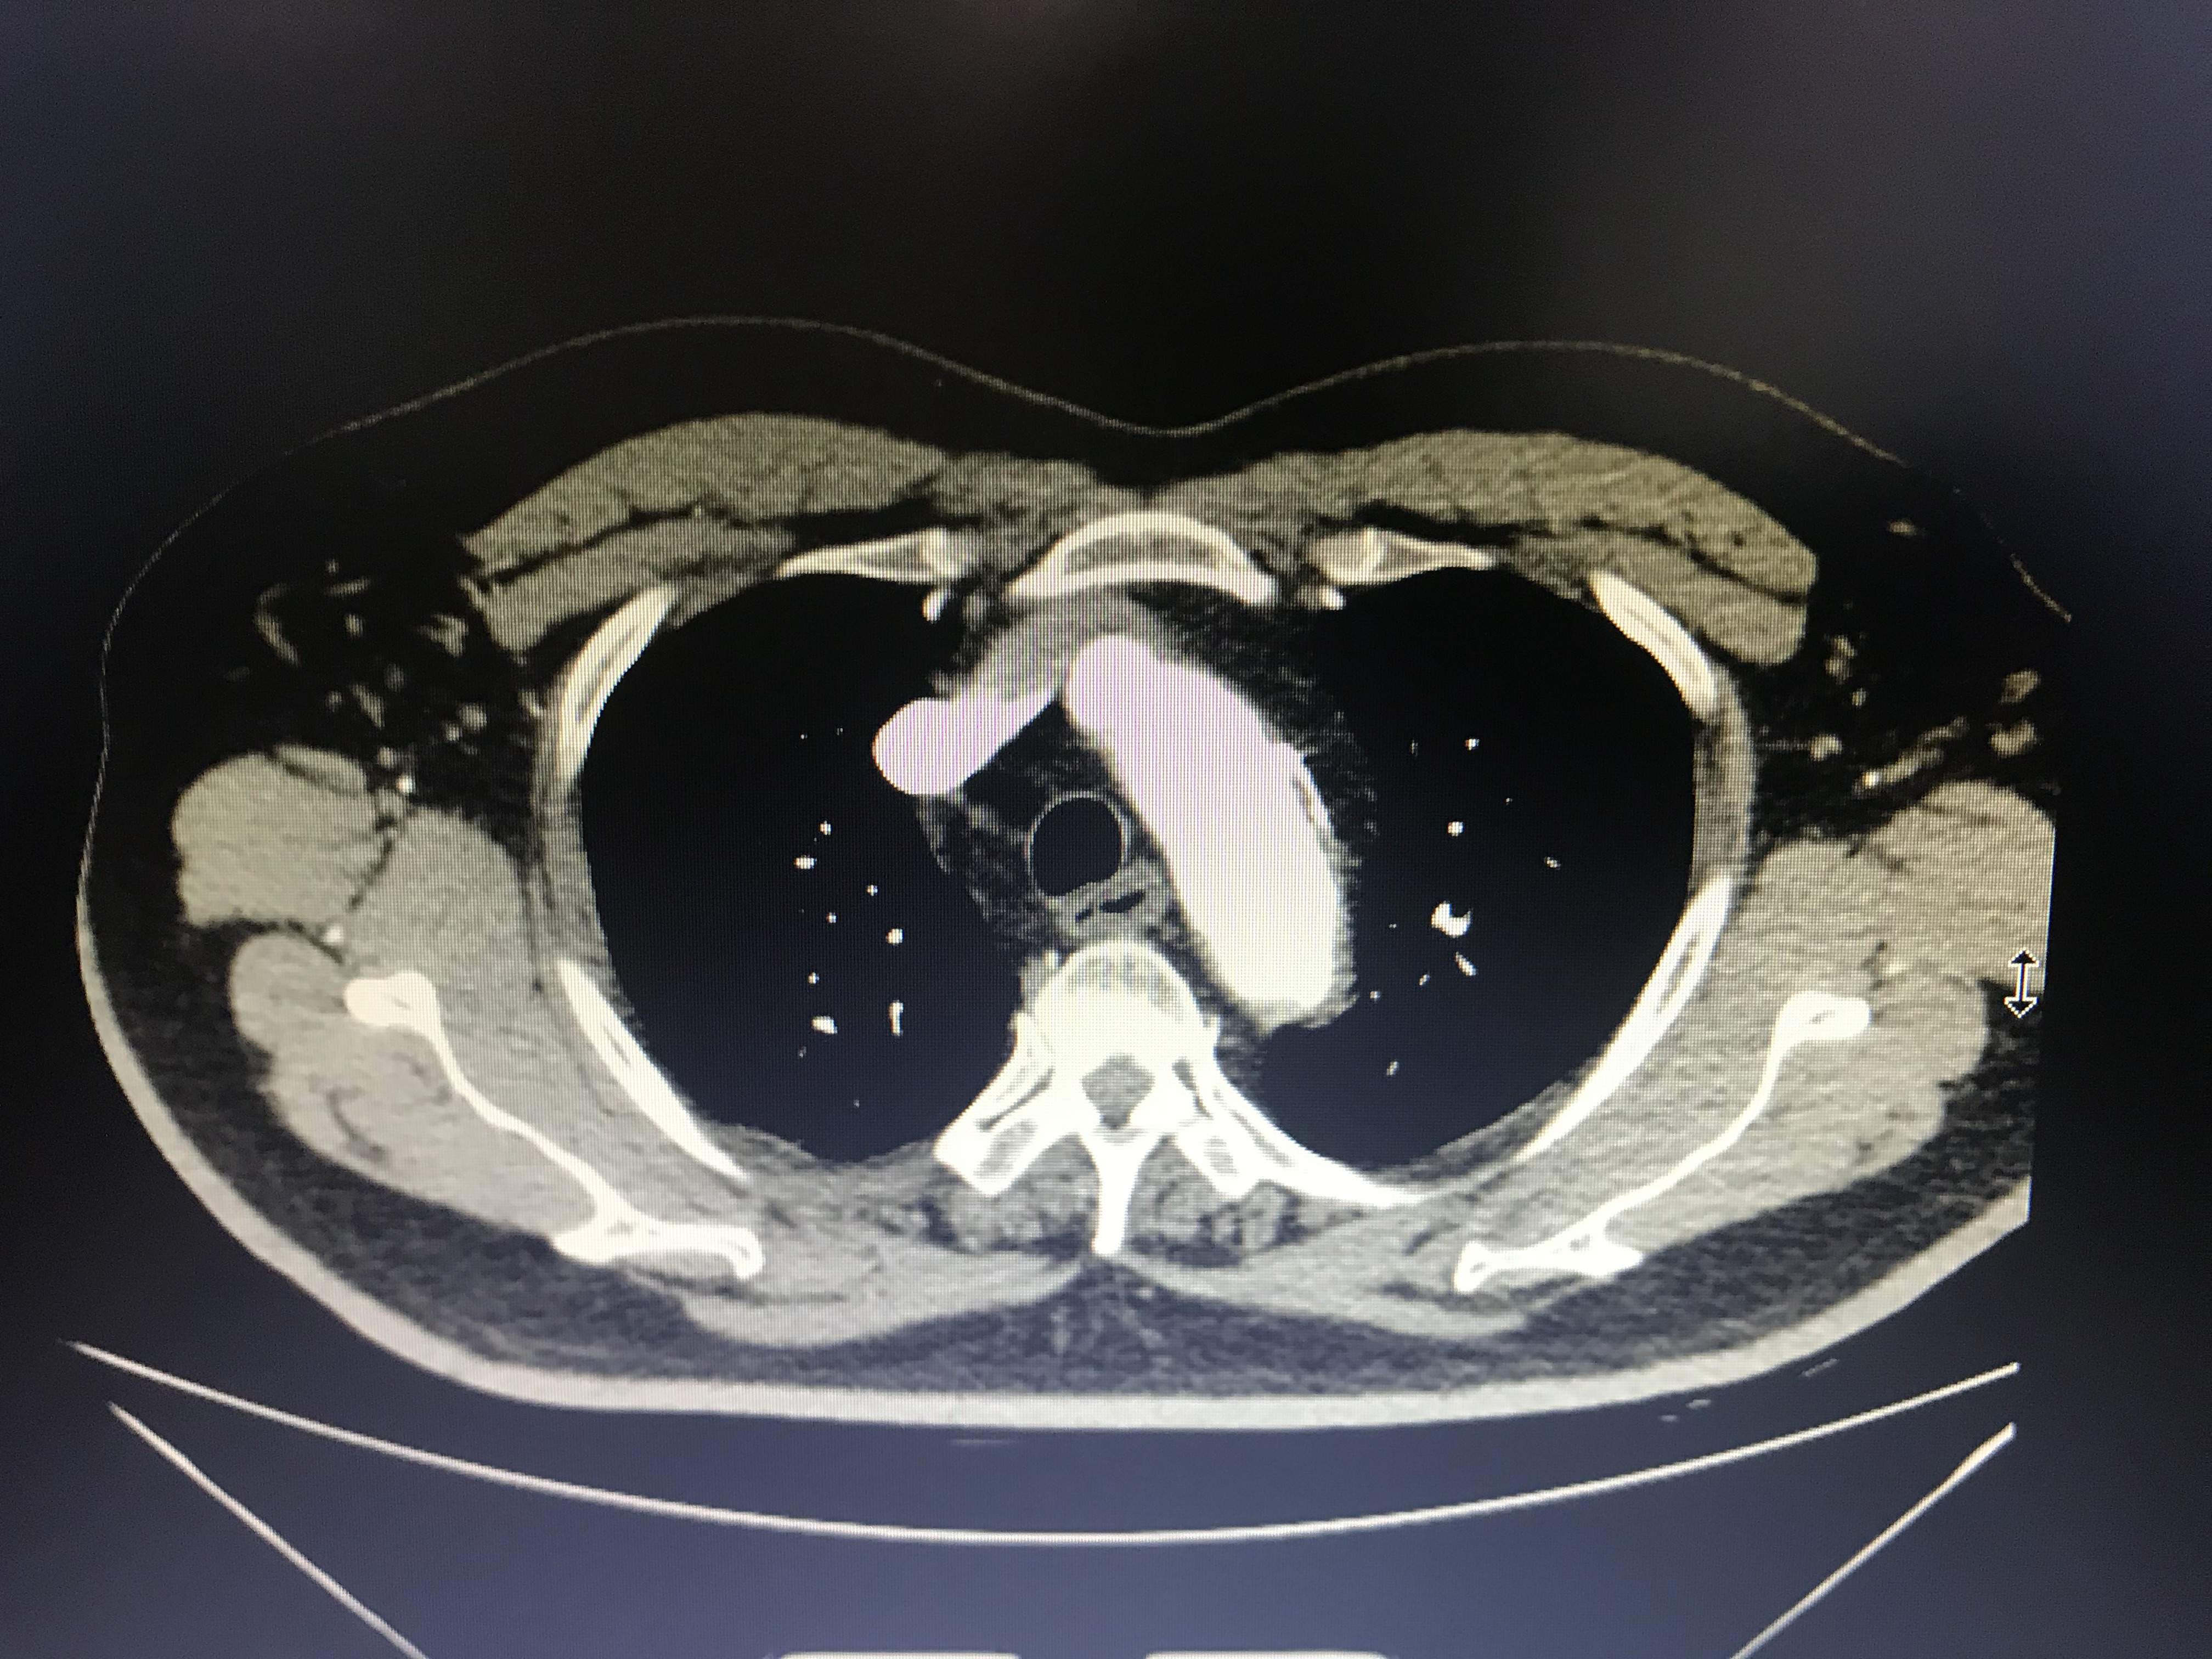

病人胸痛,这图像竟然不是主动脉溃疡?

大家帮我忙看看,到底是不是主动脉溃疡?